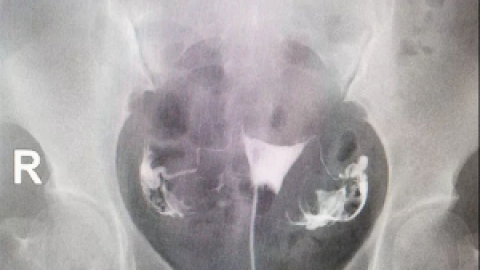

子宫输卵管造影中国专家共识[J/CD].对于输卵管性不孕症,需要检查输卵管的通畅度,主要检查方法有:(1)输卵管通液术;(2)子宫输卵管造影(hysterosalpingography,HSG);(3)子宫输卵管超声造影;(4)在腹腔镜直视下输卵管通

当医生提到输卵管检查的时候,有些建议做输卵管碘油造影,而有些则建议做碘水,两种造影的区别是什么?什么情况下需要做输卵管造影?在诊断输卵管疾病时,医生会根据患者的个人情况,选择合适的造影剂,已达到更好的造影成像。在子宫输卵管造影中,造影剂的选择至关重要。临床上根据所选用的造影剂不同分为子宫输卵管造影碘油造影和碘水造影两大...

输卵管造影和通液有什么区别很多人把输卵管造影和输卵管通液搞混淆,其实它们的实质是完全不同的。阻塞部位及宫腔形态的一种检查方法。对于指导输卵管疾病的治疗起到了确定性的作用。输卵管是否通畅的首选检查方法。输卵管通液术又称输卵管通水,是输卵管通畅性粗略检查方法之一。药液时阻力的大小及液体返流的情况,判断输卵管是否通畅的方法。...